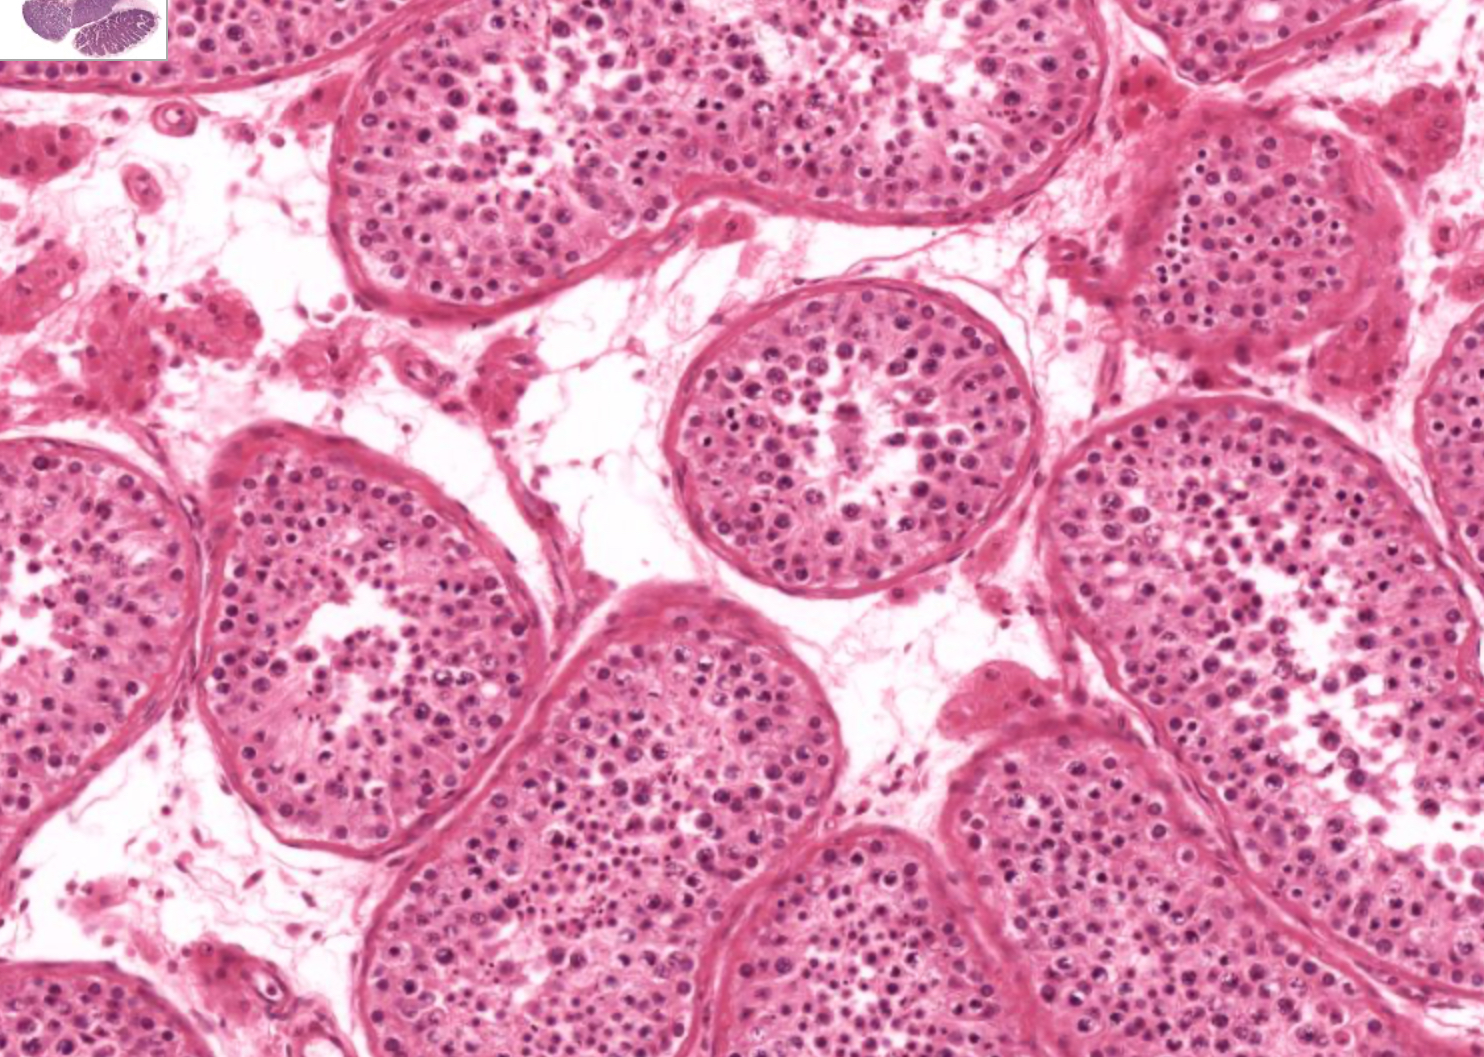

seminiferous tubule

histo; each “circle”

histo; “clumps” between circles

leydig cell

histo; larger nucleus but pretty solidified

spermatogonia

histo; large nucelus, but starting to break apart, can see little dots in the nucleus

primary spermatocyte

histo in general;

spermatid

histo specific; small condensed dark nucleus

spermatid-early

histo specific; flattened long nucleus and cell

spermatid-late

histo; flattened nucelus and cell but within the mess, has tails

spermatozoon